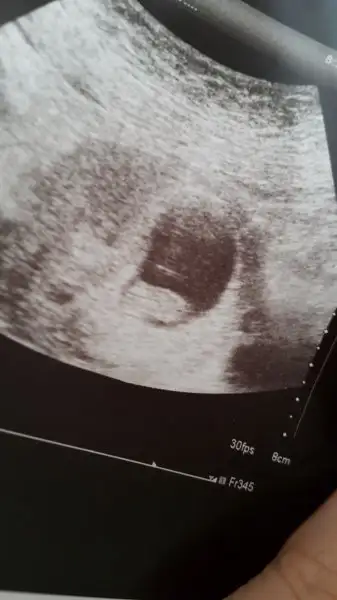

Endişe etme canım güzelce uyu Bugun yarın ilk kez tanışacaksınız hayırlı güzel haberlerle gel inşllahTatlı annisler hepinize iyi akşamlaryarın kesemizi görmeye gideceğiz 1 haftadir bu gunu bekliyordum

Icini ferah tut cok guzel haberler vericen insallah canim bizee rabbim gonlundekini versin insallahhhh❤Tatlı annisler hepinize iyi akşamlaryarın kesemizi görmeye gideceğiz 1 haftadir bu gunu bekliyordum

ben hiç anlamadım Hic merak etme canim hersey yolunda gidicek, hayirli haberlerink bekliyoruzTatlı annisler hepinize iyi akşamlaryarın kesemizi görmeye gideceğiz 1 haftadir bu gunu bekliyordum

Hadi inşallah canım güzelce uyu yarında bebeğinle ilk karşılaşmanı yap :) herşey güzel ve yolunda olacak inşallah merak etmeTatlı annisler hepinize iyi akşamlaryarın kesemizi görmeye gideceğiz 1 haftadir bu gunu bekliyordum